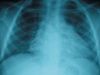

Because the patient had been born in a high-risk area, had a questionable history of blood transfusion, and had candidiasis and verrucae plana, immunodeficiency was considered. Additional laboratory studies were confirmatory. Levels of IgG were 2870 mg/dL (normal, 730 to 1500 mg/dL); IgA, 572 mg/dL (normal, 460 to 1200 mg/dL); IgM, 1117 mg/dL (normal, 50 to 240 mg/dL); antinuclear antibody, less than 40 (normal, less than 40); anti-double-stranded DNA, less than 10 IU/mL (normal, less than 10 IU/mL). She was HIV-positive. Tests for Mycobacterium avium-intracellulare (MAI) infection were negative, and her urine was negative for Cytomegalovirus. Chest films confirmed lymphocytic interstitial pneumonitis (LIP) (Figure 2). Further testing revealed that the child's mother was also HIV-positive.

Chest radiographs are essential in the diagnosis of LIP and may show bibasilar infiltrates, mediastinal widening, and hilar enlargement. Bronchoscopy with transbronchial biopsy is diagnostic. In patients who have documented HIV infection, cough, dyspnea, and classic infiltrates on chest films, LIP may be diagnosed clinically without any further invasive procedures.